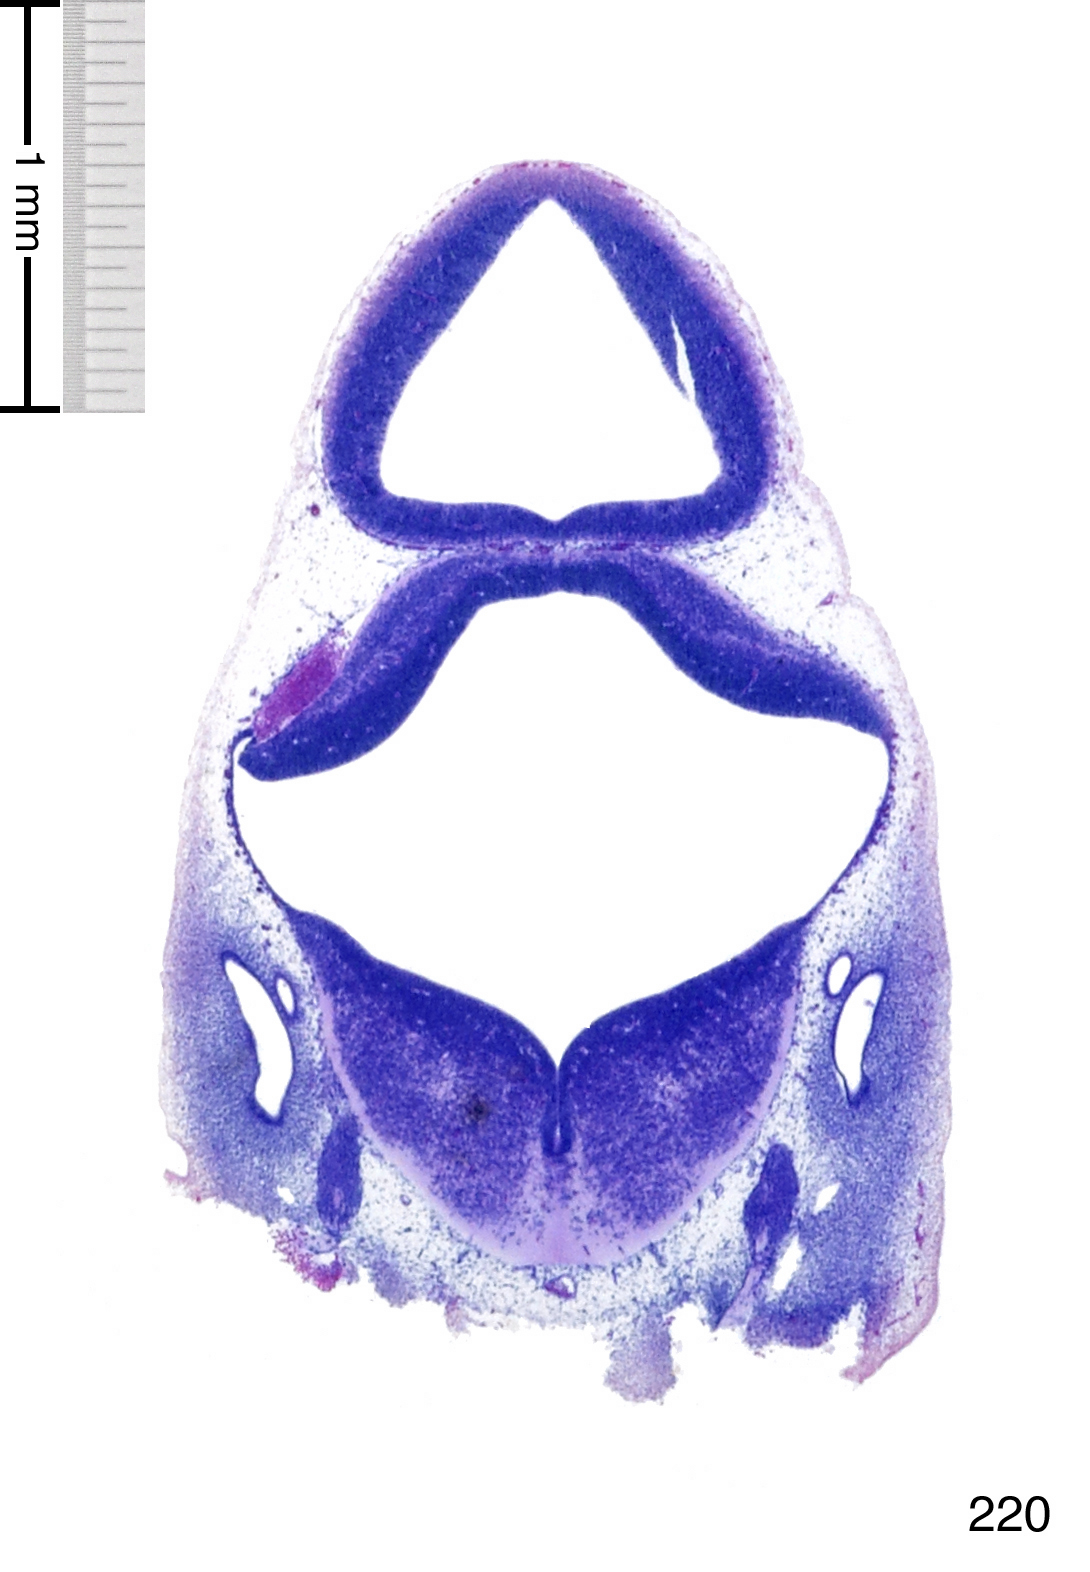

C57BL/6J GD12 Mouse Brain Atlas

Slides from U. Schambra, coronal cuts with slides at every 5th section, with a hematoxylin and eosin (H & E) stain

Currently on section 220.